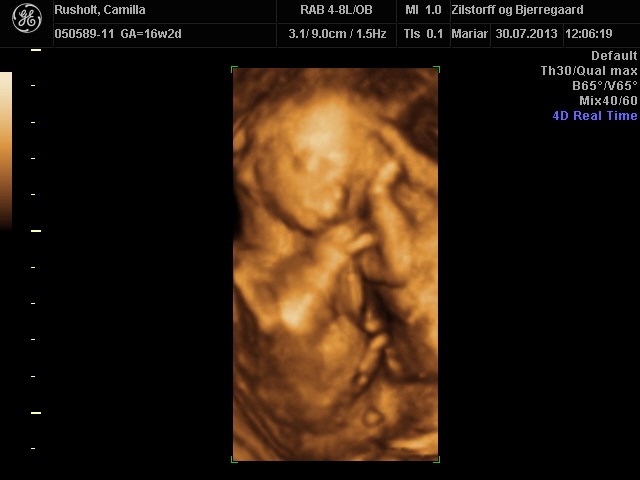

CroQuis skriver:

Årrrrrrh hvor er han fin

Hvad koster det egentlig at få 3D og alle de billeder/film med?

Vi gav 700 kr

Vi køber så også 3d/4d scanning hos dem i uge 28, og så får man så rabat på den. Den koster 1400, men vi skal kun give 1100 (fordi vi har fået kønsscanning der også), og så får vi 300 tilbage af danmark, så alt i alt 1700 kr for 3d/4d scanning samt kønsscanning med 3d